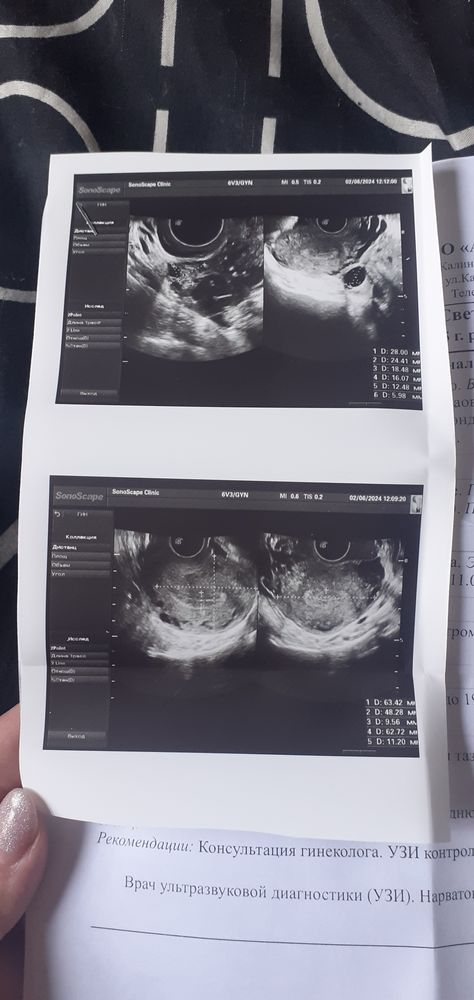

Сегодня 7 день цикла, по узи в матке все хорошо, по яичникам всё хорошо и в левом яичнике фоликул 19мм, но эндометрий 11мм., узист сказала больше чем должен быть, как будто вот вот должны начаться месячные, но это же невозможно.

Я не исключаю раннюю овуляцию, поэтому фоликул и эндометрий большие